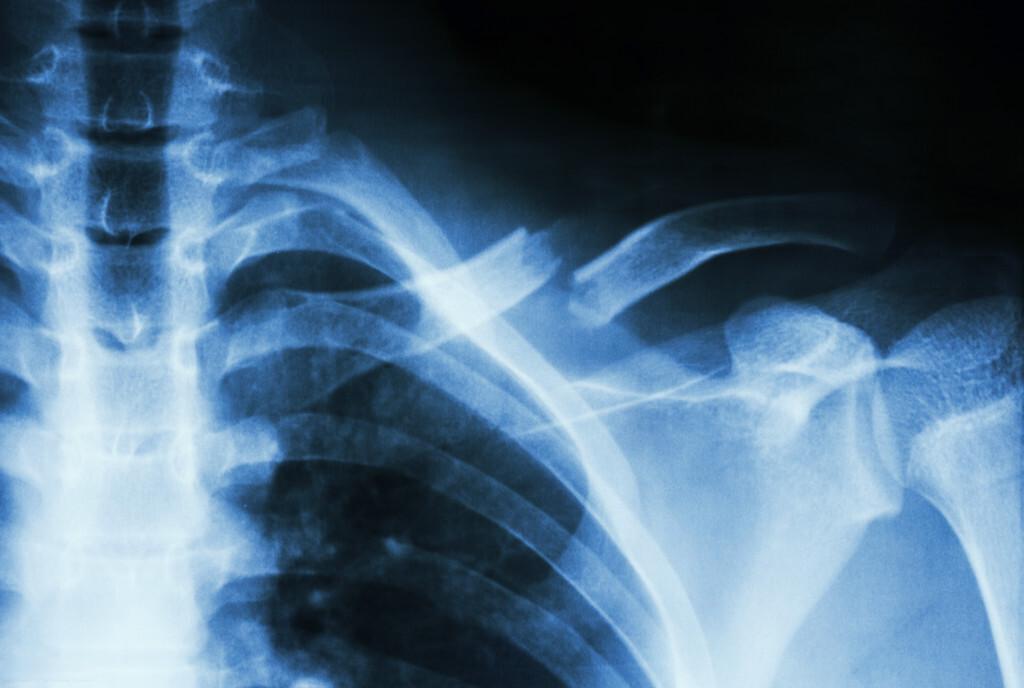

「医学笔记」——锁骨骨折

锁骨骨折通常由跌倒、运动损伤或交通事故引起。我是在一次滑雪事故中不幸受伤的。当时,我感到剧烈的疼痛,肩膀无法活动,甚至能听到骨头摩擦的声音。这些症状都是锁骨骨折的典型表现。如果你遇到类似情况,请务必立即就医,因为及时治疗对于恢复至关重要。

治疗方法通常分为保守治疗和手术治疗两种。我的情况属于无明显移位的骨折,所以选择了保守治疗,使用“8”字绷带固定。对于有明显移位或开放性骨折的患者,可能需要手术治疗。无论哪种方法,医生都会根据具体情况制定最佳治疗方案。

在康复期间,我学会了如何调整日常生活。首先,我避免了所有可能导致再次受伤的活动。其次,我严格遵守医生的复查时间表,通过X光检查密切关注骨折愈合情况。此外,我还进行了适当的锻炼,从简单的手臂活动开始,逐渐增加活动范围。这不仅有助于促进血液循环,还加快了恢复速度。